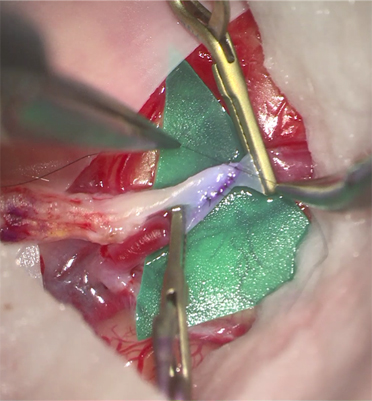

내과적 치료와 수술적 치료로 구분할 수 있는데, 허혈성 모야모야병의 경우에는 급성기에 뇌경색예방을 위한 항혈소판제제 (항응고제)를 투여 받으나, 이에 대한 장기적인 투여가 뇌졸중의 발생을 줄일 수 있다는 뚜렷한 근거는 아직까지 부족한 상태입니다. 수술적 치료는 두개내 뇌혈관의 폐쇄 및 협착으로 인한 혈역학적인 불안정을 해소하고자 뇌바깥부분의 혈관을 뇌혈관과 직간접적으로 이어주는 수술인 혈관우회수술이 대표적이고, 또한 혈역학적인 불안정으로 인해 발생하는 두개내 동맥류나 가성동맥류의 색전술 치료가 시행되고 있습니다.

두개내외 뇌혈관우회로수술, 수술 후 뇌혈관조영술 및 뇌관류CT